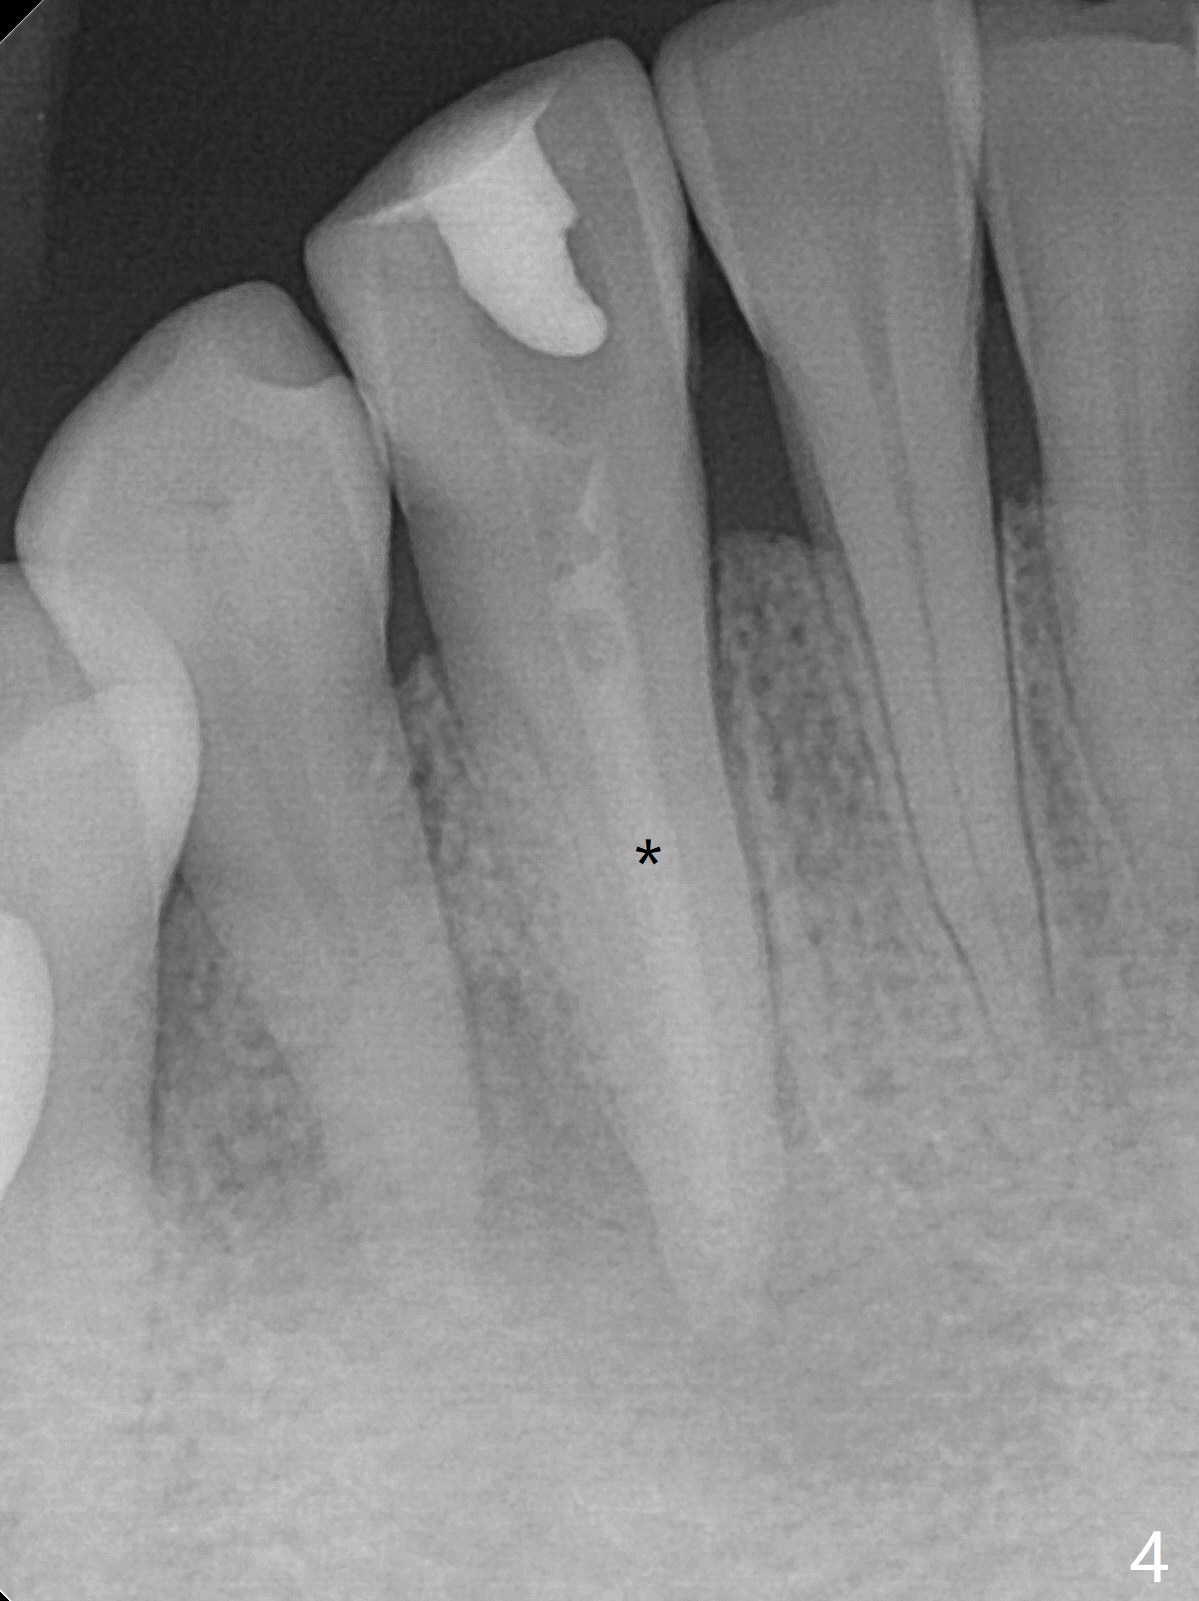

A 47-year-old woman with autoimmune hepatitis has a fistula distal to the tooth #28, but the tooth #27 is discolored and necrotic (pulpal test: 28 vital, Fig.1) with an incisal dimple (wear facet, Fig.2). Periapical radiolucency appears to involve the teeth #27 and 28. RCT is initiated at #27 through the incisal dimple. The orifice is reached immediately. Occasionally Sodium Hydro chlorite solution seems to leak out of the fistula. After debridement and placement of Ca(OH)2 paste (Fig.4 *) in the canal, the fistula is apparently shrunken (data not shown). The patient is scheduled to return 1 month.